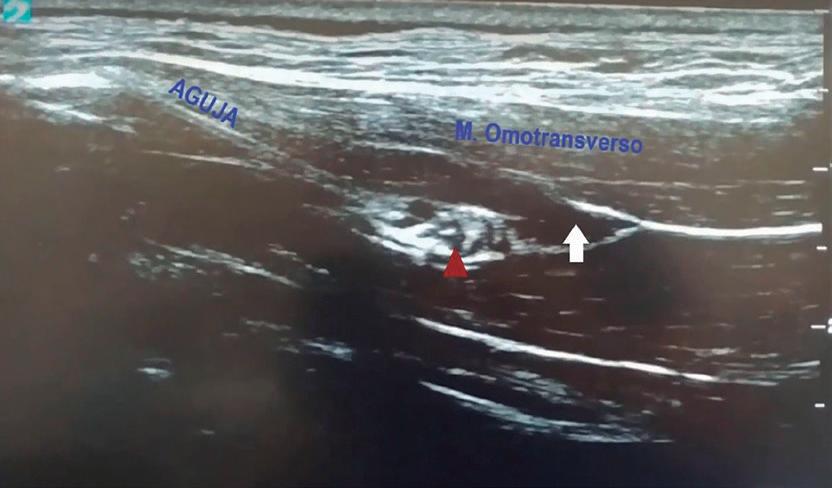

Argos 248 by Grupo Asís - Issuu